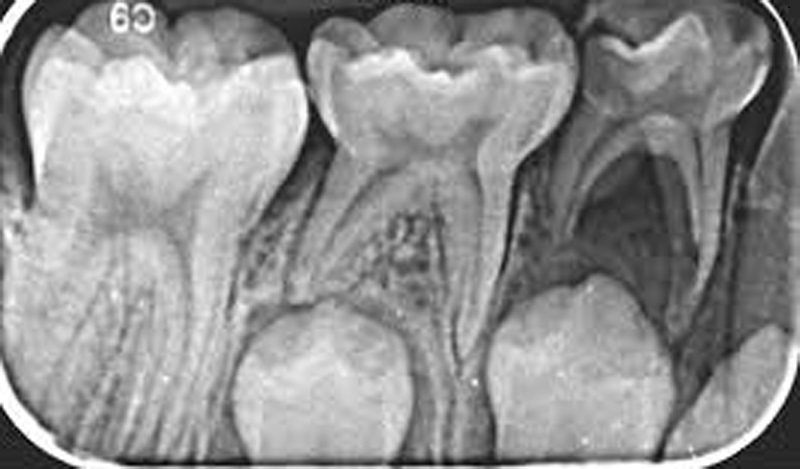

Con el tiempo, los dientes de leche cumplen su misión y se caen para dar paso a los permanentes. Estos nuevos dientes se forman en silencio bajo las encías, listos para emerger cuando el cuerpo lo necesita. Es un relevo perfectamente coordinado: los dientes temporales abren camino y los definitivos se instalan para acompañarnos toda la vida.